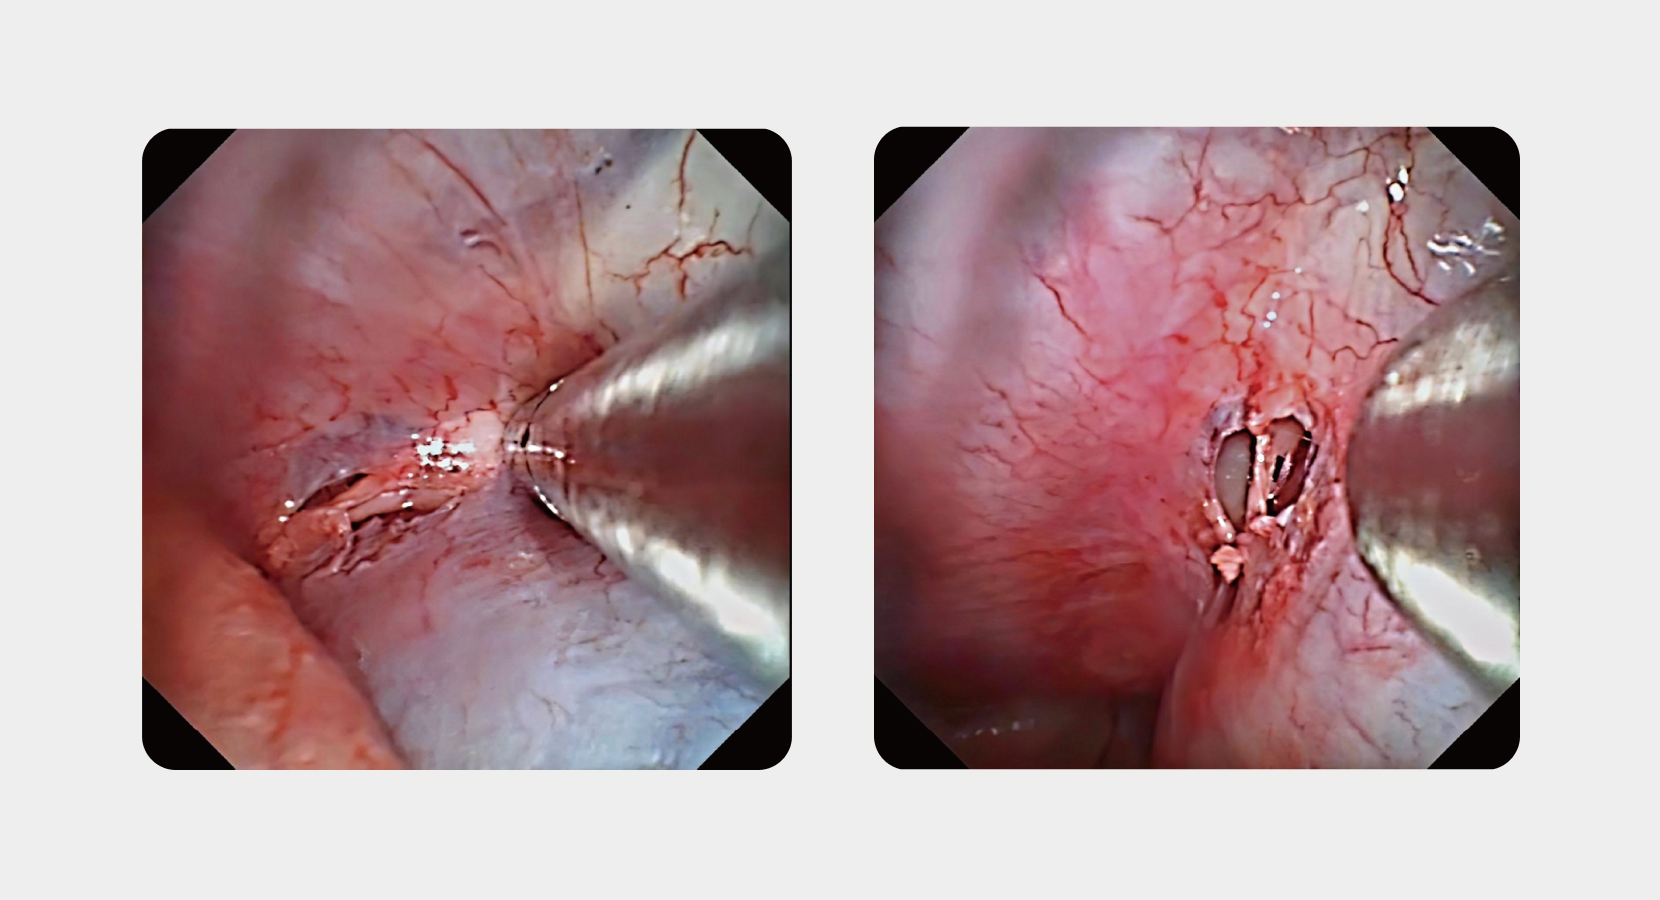

電子胸腔內窺鏡

FET-680

剛柔并濟 · 診療一體

專利直通式鉗道

3.2mm工作通道

硬質工具 直取病灶

高清圖像

靈活操作部

直通式可彎曲鉗道,可應用外科硬質工具,兼具兩者優點,可應用于胸腔診斷治療

中國發明專利 專利號:ZL202310890067.6

中國實用新型專利 專利號:ZL202321908048.3

提供比本司2.8mm通道更強的吸引力

提供比軟質工具更輕松便捷的取樣方式

為診療提供清晰可辨的鏡下反饋

手柄雙向旋轉120°,插入部上下彎曲180°